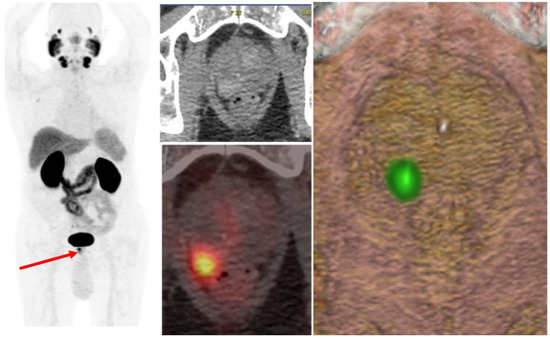

4.1. Local Recurrence